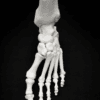

| Pathology | Pes Cavus |

| Procedure | Cole Osteotomy, Dwyer, Lateralizing Calcaneal Osteotomy, Metatarsal Dorsiflexion Osteotomy |

| Area | Midfoot |

Pes Cavus – Bone Model